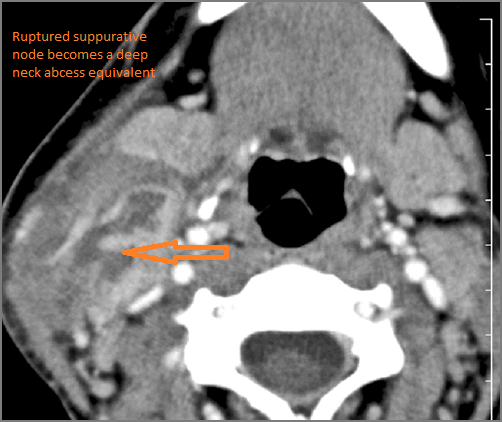

There is abscess within the adjacent deep neck, retropharyngeal and/or prevertebral spaces.

If there is suppurative cervical adenopathy the purulent material outside the lymph node(s) capsule(s).